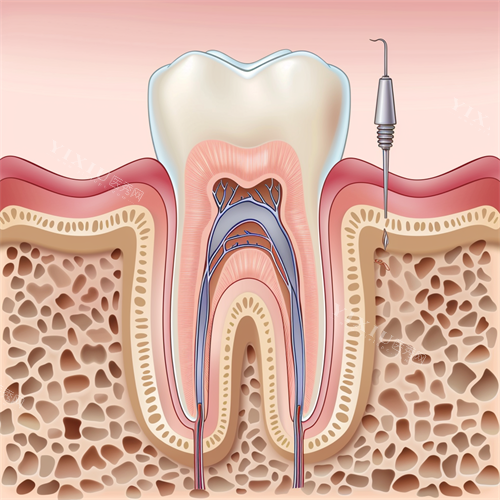

六、根管治疗价格

前牙根管治疗:390 元起

前磨牙根管治疗:690 元起

后磨牙根管治疗:1000 元起

前牙根管治疗 + 牙冠:1590 元起